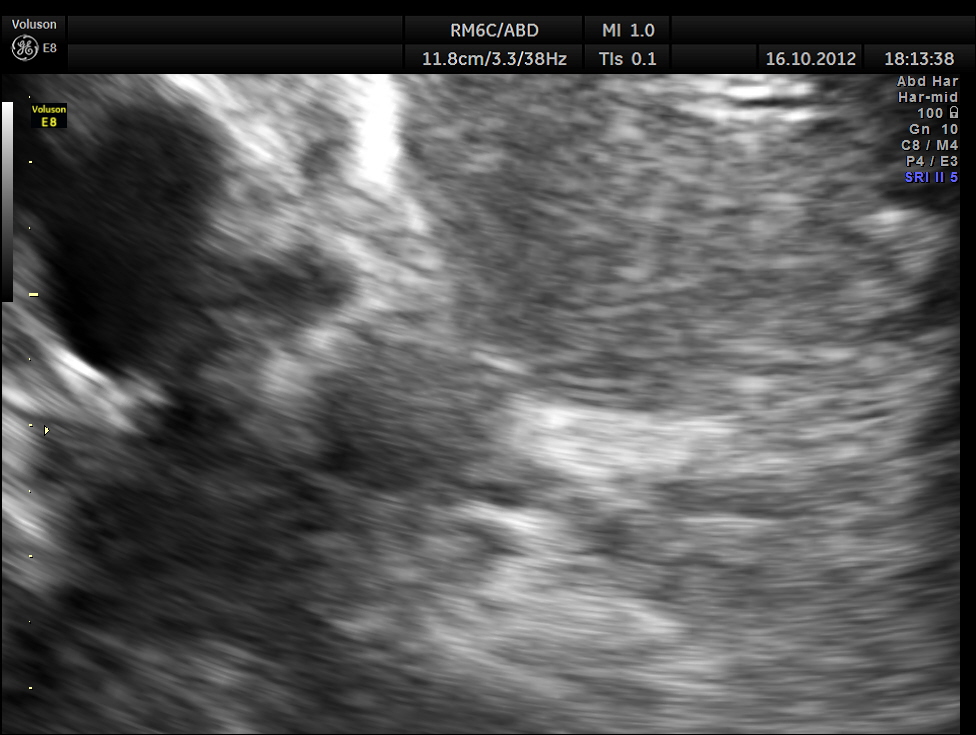

This was a 55 year old man with history of jaundice and upper abdominal pain .